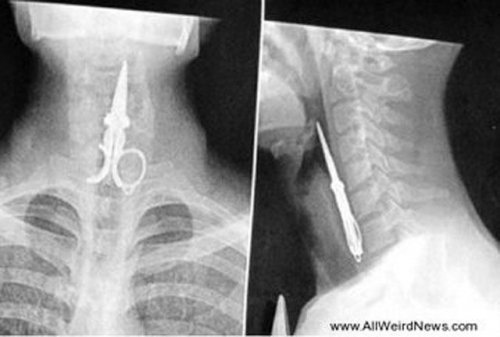

Этот парень ковырялся в зубах при помощи ножниц, но начал смеяться и ножницы провалились в горло. Он выжил и пострадал не сильно!![]()

Рентгеновский снимок ножниц, оставленных внутри желудка Пэта Скиннера (Pat Skinner) из Хёрствилля (Hurstvlle) во время операции в больнице Святого Георгия (St George Hospital), Сидней.![]()